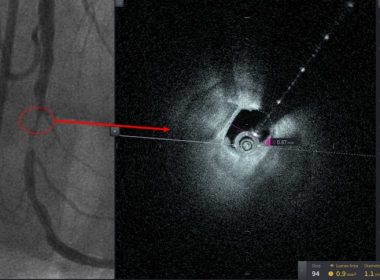

Tampa General Hospital/USF Health Interventional Cardiology Team Adopts New Intravascular Imaging Technology and Performs First Case in the World

TAMPA, Fla., May 12, 2021 /PRNewswire/ — Tampa General Hospital and USF Health’s Interventional Cardiology team has adopted new intravascular technology and successfully treated the first patient in the world. Tampa General has built a legacy as an early adopter of intravascular imaging for coronary intervention and continues to seek the newest and […]